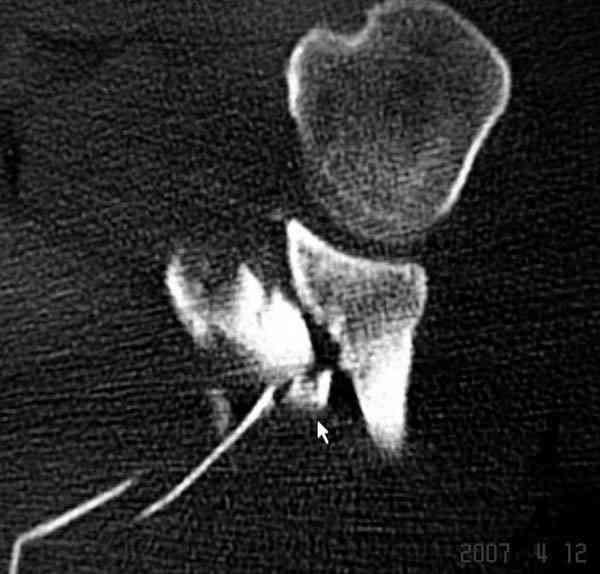

К-томографические и Трехмерные(3D)снимки крайне важны для определения внутрисуставных переломов и классификации.

Кроме анатомической классификации, переломы лопатки делятся на стабильные и нестабильные, внутри- и внесуставные и с вовлечением суставной поверхности.

Также показания к оперативному вмещательству на лопатке появляются, когда смещения суставной поверхности медиально 9 и более мм и при угловом смещении суставной поверхности 40 и более градусов.